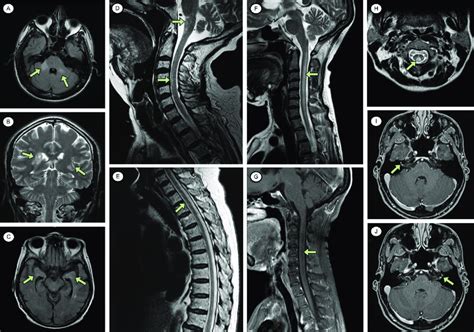

Hey guys! Ever wondered what happens when your brain gets a little… off ? Well, when doctors suspect something’s amiss in your central nervous system (CNS) – that’s your brain and spinal cord, for those keeping score – they often turn to diagnostic imaging. This can involve a variety of techniques, such as MRI (magnetic resonance imaging), CT scans (computed tomography), and even ultrasounds. These methods allow them to peer inside and see what’s going on. But what exactly are they looking for? And what do those “other abnormal findings” actually mean ? Let’s dive in and explore some of the common things that can pop up on these scans, shall we?

• MRI (Magnetic Resonance Imaging): This is the gold standard for many CNS investigations. Using powerful magnets and radio waves, MRI creates incredibly detailed images of the brain and spinal cord. It’s fantastic for spotting subtle changes in tissue, like tumors, inflammation, and even the damage caused by strokes.

On imaging, tumors can appear as masses with varying characteristics depending on their type and aggressiveness. They may show up as bright or dark spots on MRI, and they can sometimes cause swelling or displacement of surrounding brain structures.

• Ischemic Stroke: In this case, there’s a blockage, leading to brain tissue death. On an MRI, early signs might include subtle changes in the affected areas. CT scans can also detect ischemic strokes, especially after several hours.

• Hemorrhagic Stroke: This involves bleeding in the brain. CT scans are particularly good at detecting bleeding, which appears bright on the images. The location and extent of the bleeding help determine the severity and the best course of treatment.

• Encephalitis: Inflammation of the brain itself. This can be caused by viruses (such as herpes simplex) or other infections. MRI can show areas of inflammation and damage.

• Abscesses: Collections of pus in the brain. These typically appear as round masses with a thick wall on imaging.

Demyelinating diseases damage the myelin sheath, which is the protective covering around nerve fibers. Multiple sclerosis (MS) is the most well-known of these. On MRI, MS often appears as multiple areas of inflammation and damage in the brain and spinal cord. These lesions can vary in size and location.